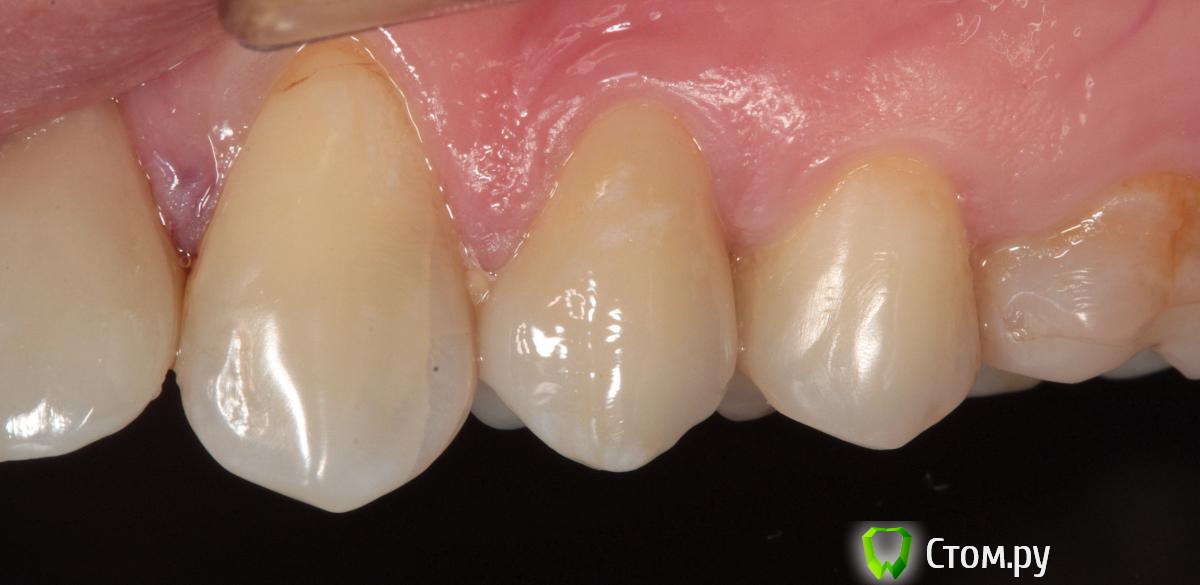

SDC Опубликовано 19 ноября, 2014 Поделиться Опубликовано 19 ноября, 2014 (изменено) Prettau, извините, не знаю, как редактировать название темы. Здравствуйте всем. В хирургическом много практиков, а по протетике - много теории)). Итак, разбавляю вино. (теория вечна)Протезирование премоляров коронками Преттау с нанесением керамики вестибулярно.Много фото, прошу прощения, поэтому без радикала, превью. Наверное даже так лучше, потому, что по клику откроются не сжатые фото, а радикал жмет.Протезирование в течение 2 недель. Фиксация на фуджи, без коффердама, но в сухих условиях (коффер не поставить по причине глубокий дистальной границы препарирования на обоих премолярах - глубокий кариес проксимальных поверхностей в анамнезе)Рг-контроль на предмет остатков цемента и на последнем фото удаленные излишки цемента на перчатке. Изменено 19 ноября, 2014 пользователем SDC 7 Ссылка на комментарий

SDC Опубликовано 20 ноября, 2014 Автор Поделиться Опубликовано 20 ноября, 2014 Хорошая работа! Единственно на 26 я бы пломбу поменял заранее, чтобы в будущем контакт не нарушать. Фуджи One или Plus? Разве первый требует изоляции коффером?Наверно, на 16? Она ~ 1 год назад сделана, перед фиксацией была полировка пломб на контактных поверхностях соседей. Фуджи 1, Обеспечение хорошей изоляции, необходимо для любого цемента, в данном случае несколько нитей ультрапак в проблемных местах. Ссылка на комментарий

SDC Опубликовано 20 ноября, 2014 Автор Поделиться Опубликовано 20 ноября, 2014 Точно) Смотрел по фото окклюзионных поверхностей. Согласен по поводу хорошей изоляции, она нигде лишней не будет, но обратил на это внимание потому что в аннотации к фуджи написано: "Просушите ватным тампоном или слегка обдуйте воздухом. НЕ ПЕРЕСУШИВАЙТЕ. Подготовленнаяповерхность зуба должна выглядеть влажной (блестящей)." - 100% цитата. На мой взгляд коффер все таки слишком круто при таких допусках.Как раз с коффером достичь подобных характеристик поверхности легче.В данном случае платок лежал на уступе, не получилось. 1 Ссылка на комментарий

SDC Опубликовано 20 ноября, 2014 Автор Поделиться Опубликовано 20 ноября, 2014 Отличный результат. Позвольте несколько вопросов.СВШ в боковых не ставите вообще,если да,то по какой причине?Как думаете антагонисты не будут истираться?Вы как-то меняете анатомию контакта при глубоких дефектах и недостатка сосочка?Спасибо.Спасибо Роман.По поводу штифтов. На самом деле, не имеет значения для меня.Важно, что не было титановых во фронтальном отделе (открываются при редукции тв.тк. небольшой объем композита вокруг штифта, что приводит к хрупкости билдапа и иногда металл.штифты светят через композит и керамику)Антагонисты истираться будут, а цирконий - нет. Что поделаешь.Сейчас мы с техником делаем нанесение вестибулярно и по скатам бугров, для уменьшения негативного эффекта повышенной прочности циркония и ускорения сдаваемости.контакт всегда площадочный, пятно контакта в корональной 1/4.Дефицит мягких тканей керамикой никогда не восполняем. Моделировка коронки максимально анатомична. Ссылка на комментарий